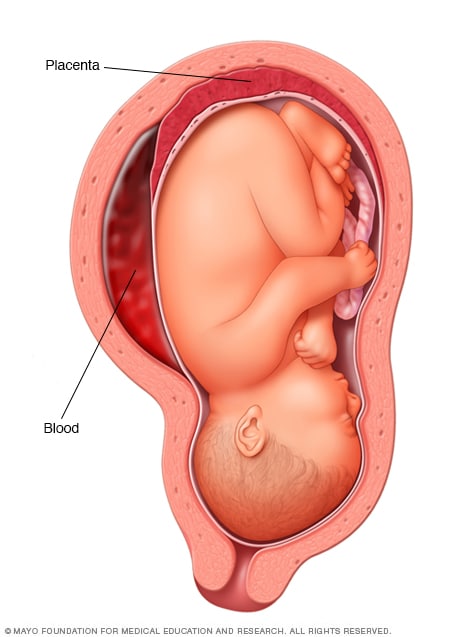

Околоплодный пузырь и плацента: структура и функции